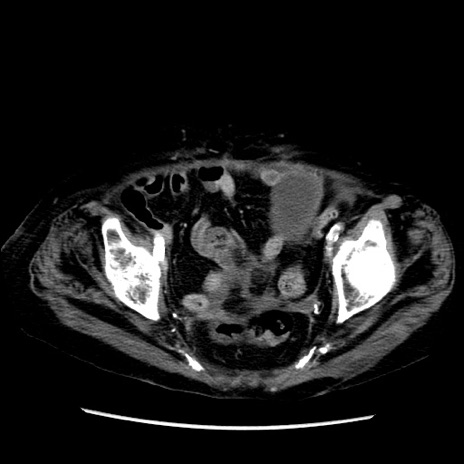

症例14(横断像)

【症例】 90歳代女性

【主訴】 腹痛・嘔吐

【現病歴】今朝から左側腹部痛を認めた。 経過観察していたが、嘔吐を認めたため来院。

【既往歴】 子宮癌術後

【身体所見】 意識清明、BP 127/54mmHg、P 98bpm Sp02 95%(RA)、BT 35.8°C、腹部平坦・軟腸ぜん動音聴取良好、右下腹部圧痛(+) 反跳痛なし

【データ】WBC 9800、CRP 0.46